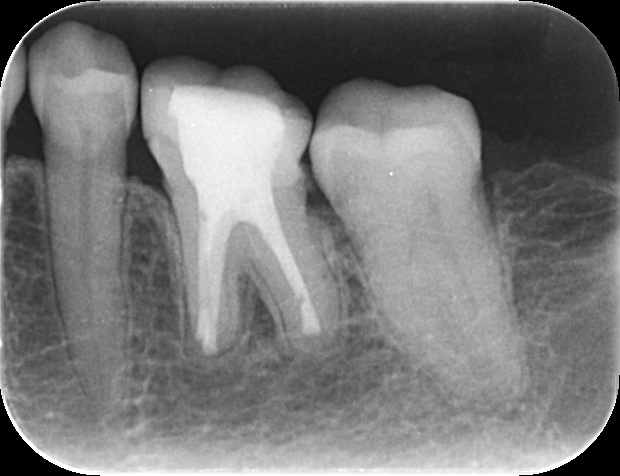

症例 再根管治療後の外科的歯内療法 2025.11.12 【背景】 ・60代女性。 他院で処置するも治らず、専門医による根管治療を希望し来院 外科的歯内療法の可能性を説明し、通法通り処置後、セラミックにて修復 その後、2年ほど経過し、根尖に病変を認めた為、外科的歯内療法へ移行し、 1年経過後のレントゲン写真にて治癒確認 歯内療法完了後 外科的歯内療法直後 1年経過時のレントゲン 【総評】 処置前の診査診断にて、治療の成功率や、外科的歯内療法の必要性について、必ず説明していますが、 一定期間が過ぎてしまうと忘れてしまう患者様は一定数いらっしゃいます セラミック修復した歯を壊す必要がなく、また、抜歯からインプラントへ移行する可能性を減らすことができるため、 難易度は高い処置ですが、専門医で対応することの意義は大きいと感じる症例をご紹介しました 根管治療でお困りの方や、クリニックの関係者の方は、ご紹介フォームからお気軽にお問い合わせください この記事のタイトルとURLをコピーする